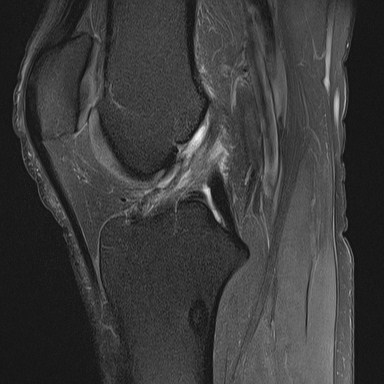

Caso haja suspeita de fratura associada, a radiografia é o exame inicial para a investigação. Caso a radiografia não identifique fraturas, mas a suspeita de lesão do LCA persista, a ressonância magnética (RM) se torna o próximo passo diagnóstico, pois permite visualizar a integridade do ligamento, meniscos e outras estruturas internas do joelho.